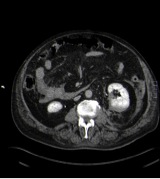

No se encuentra extravasado de contraste en la fase arterial por lo que se descarta lesión vascular. Existe una alteración de la anatomía normal del polo inferior del riñón izquierdo con solución de continuidad del parénquima (laceración) y una imagen en la parte posterior del mismo compatible con hematoma.